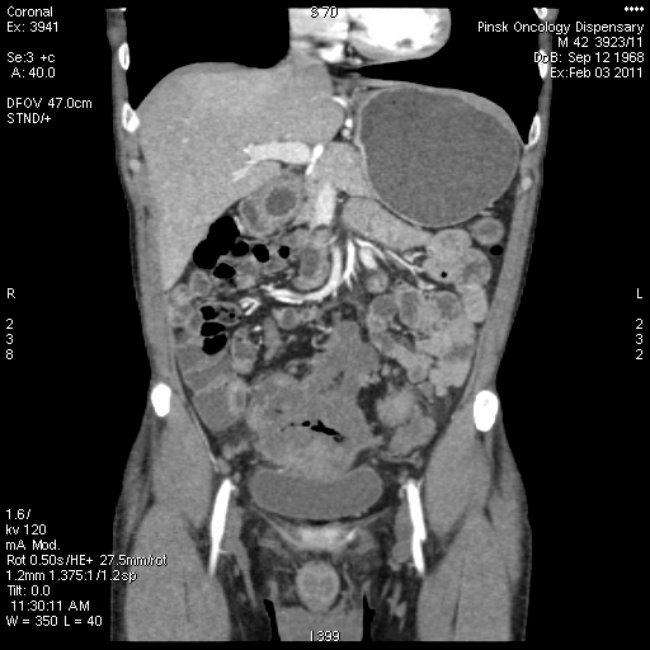

- Компьютерная и магнитно-резонансная томография. Эти методики помогут уточнить диагноз, послойно определив опухоль.